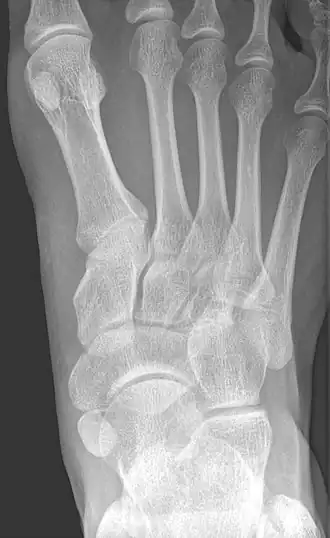

-

From left to right: Type 1, 2 and 3 -

Type 2 -